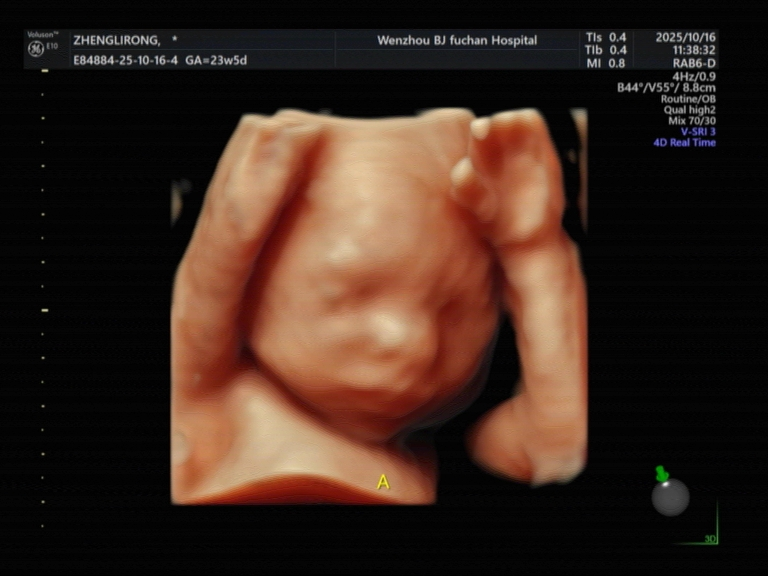

双重检查,耗时翻倍以上:医生需要为两个宝宝分别进行全身系统的畸形筛查,包括两个头、两个心脏、四条胳膊、四条腿等。这不仅仅是看两眼那么简单,每个胎儿都需要采集标准切面,测量数据。如果一个宝宝位置不好,等待和尝试的时间会更长。

更高的设备性能需求:为了更清晰地分辨和观察两个相互重叠的结构,医院可能需要动用更高阶的超声设备,其成本和维护费用也更高。